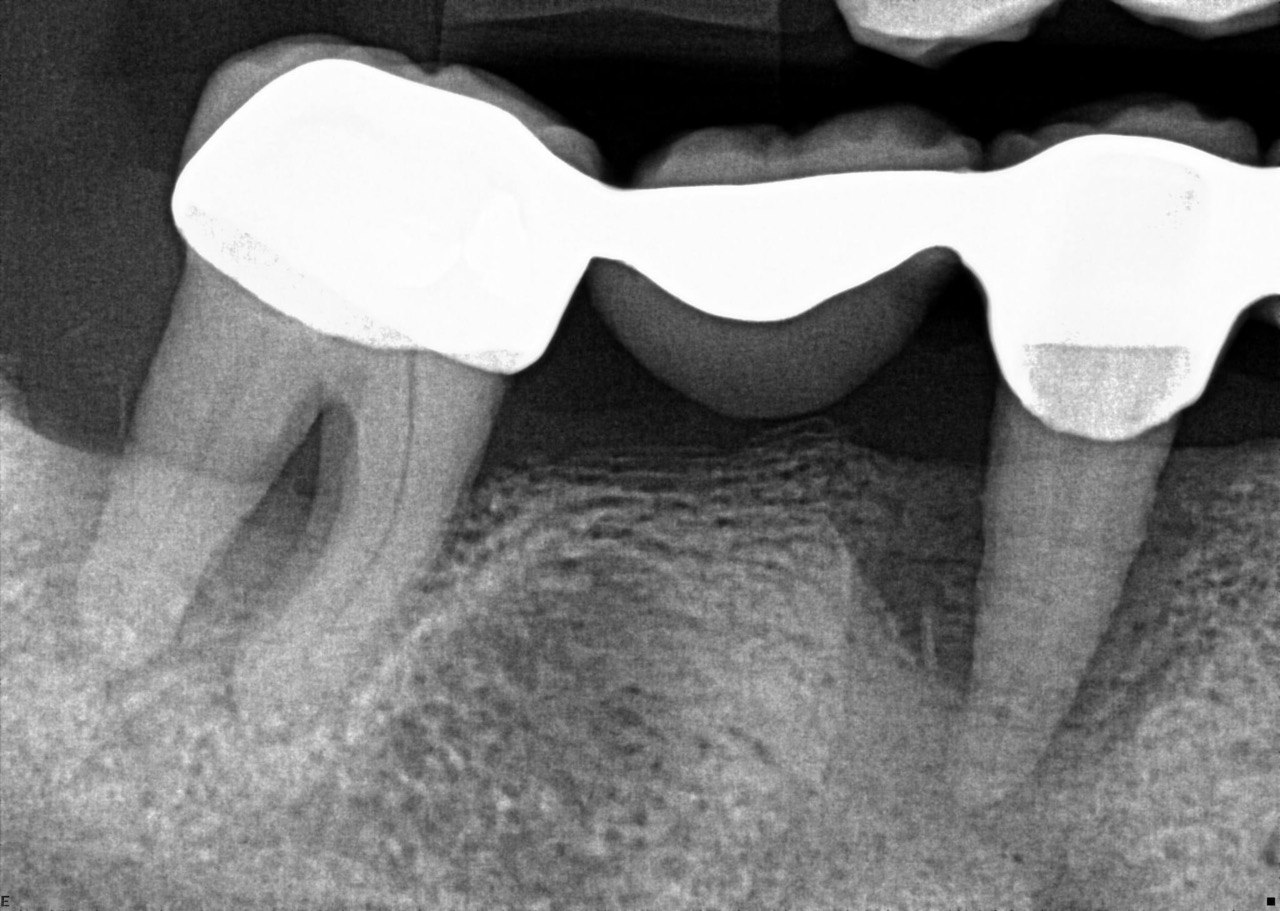

31. What option cannot be selected for the tooth # 3.6?

32. What options cannot be seen in the print of this X ray?

33. What options cannot be seen in the print of this X ray?

34. What option can be selected for tooth # 4.6?

35. What options cannot be selected for the tooth # 1.5?

36. What options cannot be selected for the tooth # 3.7?

37. What options can be selected for tooth # 1.2?

38. What option can be seen in the print of this X ray?

39. What options can be selected for the print of this X ray?

40. What cannot be seen in the print of this X ray?